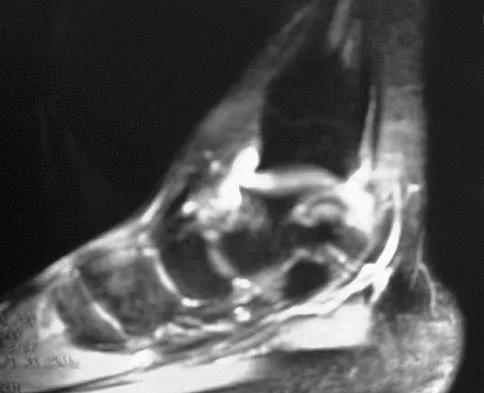

Figure 7 shows the MRI scan of a 23-year-old competitive rugby player who has anterior ankle pain and swelling. He states that he has been playing for many years and has sprained his ankle several times. Examination will reveal what specific hallmark feature?

Explanation